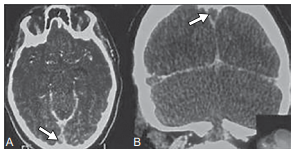

Mulher de 32 anos, previamente hígida, iniciou com cefaleia intensa e progressiva há cinco dias, associada a visão turva e episódios de vômito. No exame físico, apresenta papiledema bilateral e discreta hemiparesia direita. A tomografia computadorizada de crânio com contraste encontra-se a seguir.

Enunciado 4395429-1

Com base nesses achados, qual é o diagnóstico mais provável e sua opção terapêutica inicial.